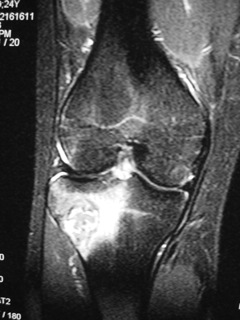

MRI (Fig. 4-7)

• Central low signal intensity with peripheral enhancement on T1-weighted images

• Heterogeneous high signal intensity with low signal in surrounding sclerotic bone on T2-weighted images

Fig. 4

Fig. 5

Fig. 6

Fig. 7

Fig. 4-7: MR imaging of a benign fibrous histiocytoma of the proximal tibia demonstrates a heterogeneous high signal intensity and low signal intensity with surrounding sclerotic bone on T2-weighted images. T1-weighted images show low signal intensity. No soft tissue mass is visible.